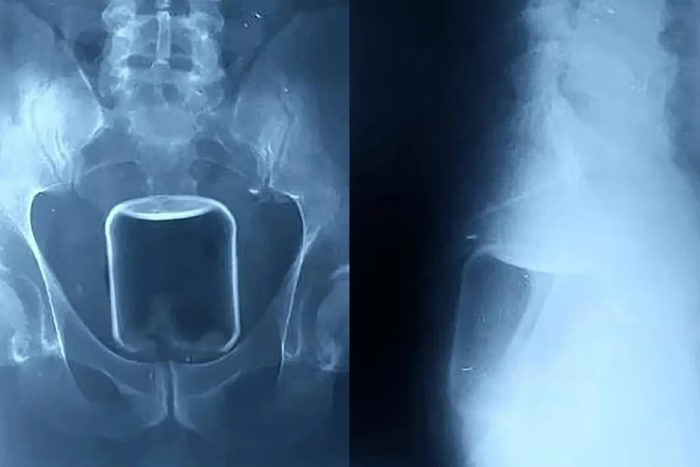

Imagens de raio-X divulgadas pelo hospital mostram o copo de vidro alojado na parte superior do reto e avançando em direção ao intestino superior. Além do copo, os profissionais de saúde removeram também um preservativo e lubrificante, provavelmente usados durante o ato sexual.